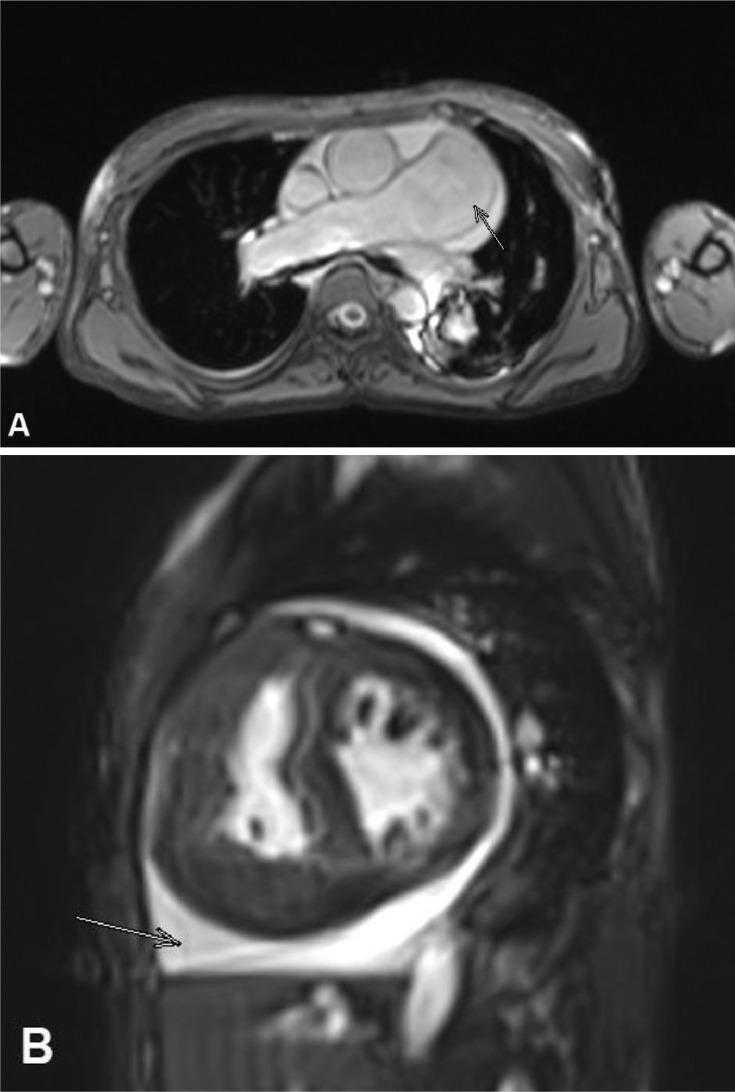

Double outlet right ventricle (DORV) is a congenital cardiac malformation that occurs in 1%-3% of individuals with congenital heart defects. Cardiac magnetic resonance imaging (MRI) may play an important role in the anatomy of the ventricular septal defect, functional status of both ventricles, and in identifying any residual stenosis or regurgitation or coexistent anomalies. Here, we present a case of a 28-years-old woman who came to our emergency department with shortness of breath. The patient felt shortness of breath on exertion and improved with rest. Clinical examination showed no abnormalities except low oxygen saturation of 65%. After echocardiography and cardiac MRI were done, it was concluded that she had a double outlet right ventricle with peri membranous ventricular septal defect (VSD), pulmonary hypertension, and pericardial effusion. This study highlights the role of cardiac MRI in assessing DORV.

右心室双出口(DORV)是一种先天性心脏畸形,在先天性心脏缺陷患者中发生率为1%-3%。心脏磁共振成像(MRI)在室间隔缺损的解剖结构、双心室功能状态以及识别任何残余狭窄或反流或并存异常方面可能发挥重要作用。在此,我们报告一例28岁女性患者,她因呼吸急促前来我院急诊科就诊。患者在运动时感到呼吸急促,休息后症状改善。临床检查除氧饱和度低至65%外无异常。经超声心动图和心脏MRI检查后,得出结论她患有右心室双出口合并膜周部室间隔缺损(VSD)、肺动脉高压和心包积液。本研究强调了心脏MRI在评估DORV中的作用。